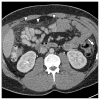

Results: The most common chest CT findings in this case series were pleural effusions and internal mammary and cardiophrenic lymphadenopathy. Pulmonary parenchymal findings included peripheral lung nodules of 1-3.5 cm in size with surrounding ground-glass opacity; many nodules had a linear track to the pleural surface that may correspond to the worm's burrow tunnel. Pericardial involvement (5/8 patients) and omental inflammation (5/7 patients), which are uncommon in Asian paragonimiasis, were common in this series.

Conclusion: Pleural and pulmonary features of North American paragonimiasis are generally similar to those reported from Asia. The presence of a track between a pulmonary nodule and the pleura may help distinguish paragonimiasis from mimickers, including chronic eosinophilic pneumonia, tuberculosis, fungal infection, or malignancy. Pericarditis, lymphadenopathy, and omental inflammation were more common in our series than in reports on paragonimiasis from other regions. These differences may be related to the infecting parasite species or to the fact that radiologic examinations in the present series were performed relatively early in the course of infection.